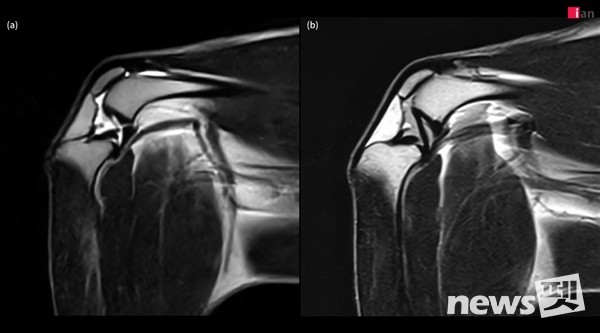

2023년 말부터 본격 가동된 이안동물의학센터의 AI 기반 MRI 소프트웨어는 딥러닝 알고리즘을 활용해 노이즈를 효과적으로 제거하고, 이미지 선명도를 대폭 향상시켰다.

특히 무릎 관절처럼 작은 구조물들이 복잡하게 얽혀 있는 부위에서 기존 영상 기법으로는 명확하게 파악하기 어려웠던 인대, 연골, 활액낭 및 인접한 근육 등의 세부 구조물까지 뚜렷하게 확인할 수 있어 정밀 진단에 도움이 되고 있다.

이안동물의학센터는 “정형외과에서 무릎 질환은 MRI로 진단하기에 가장 까다로운 분야 중 하나”라며 “AI 기술을 통해 MRI의 화질이 개선됨에 따라 십자 인대 파열, 연골 손상, 활액막 질환, 힘줄 질환 등 다양한 무릎 질환을 보다 빠르고 정확하게 진단할 수 있게 됐다”고 밝혔다.